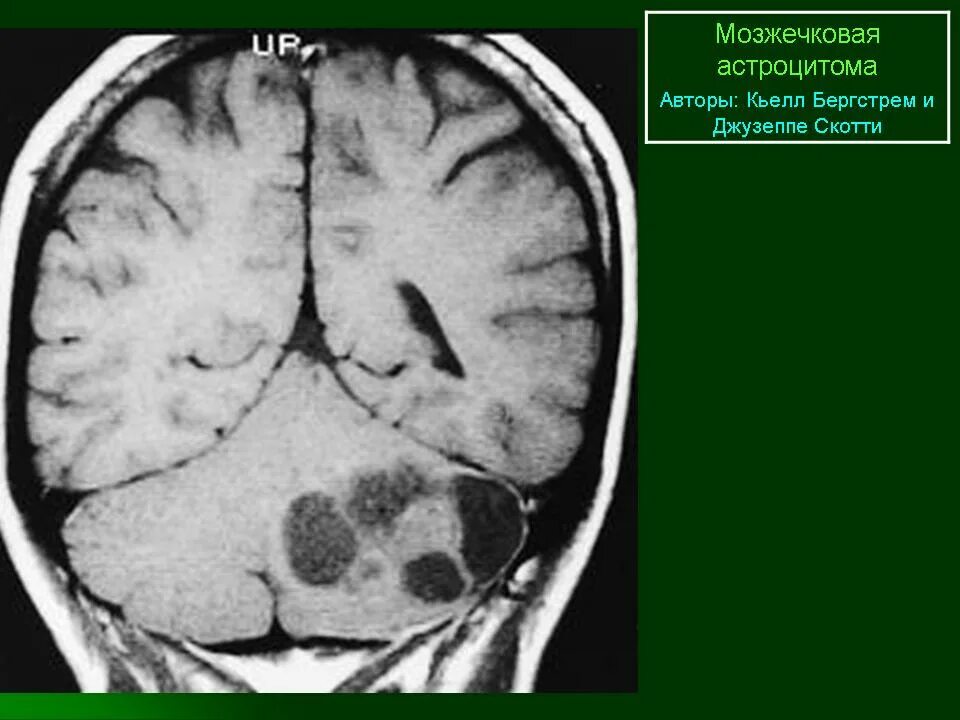

Астроцитома головного мозга прогноз после операции